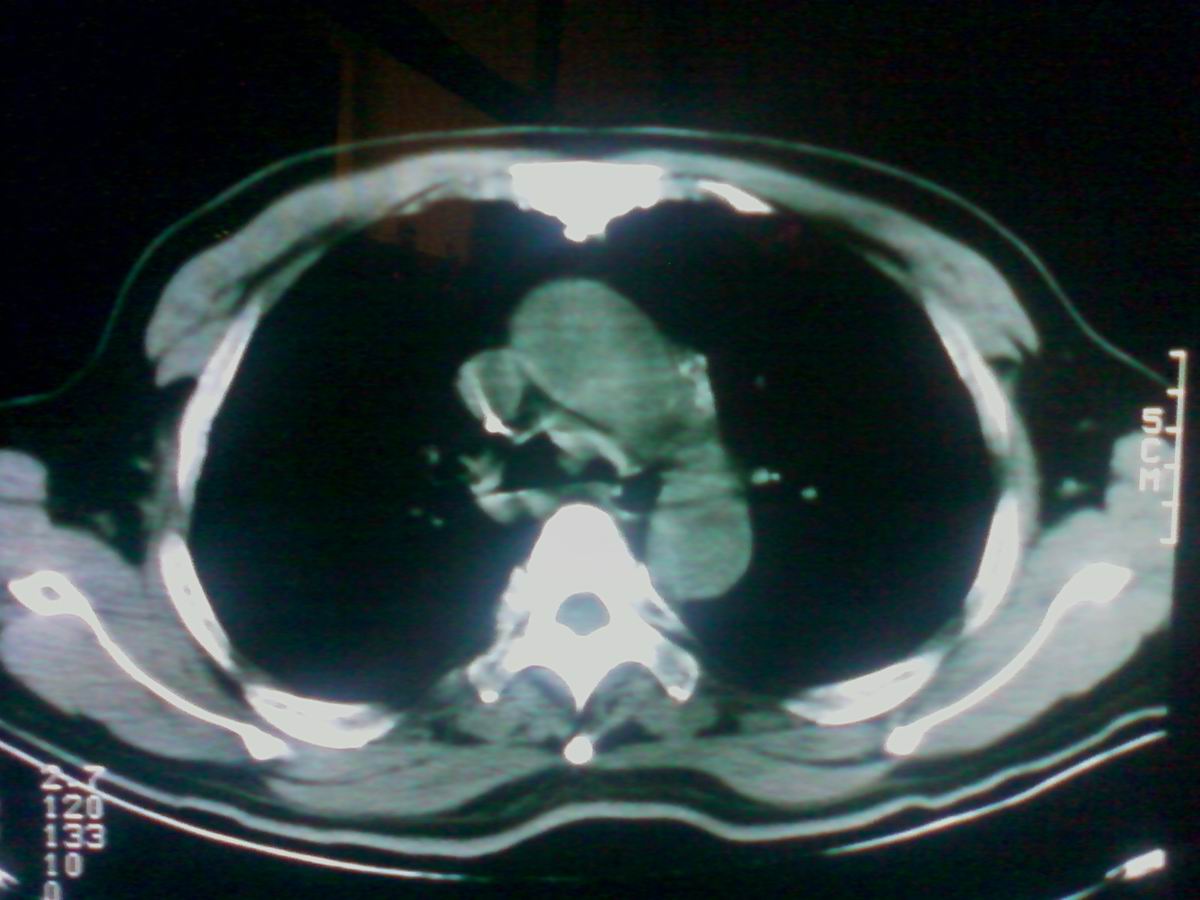

标题: CT25801:患者男性,65岁,临床提示双肺可闻及广泛罗音,看 [打印本页]

标题: CT25801:患者男性,65岁,临床提示双肺可闻及广泛罗音,看

气管后部见半圆形软组织密度病灶,考虑占位,建议气管镜除外鳞癌。

气管上段的肿瘤多为良性乳头状瘤,气管下段的肿瘤多为鳞癌,气管中段的良恶性各占一半。本例位于气管下段,先按恶性处理。不过纤支镜是免不了的。